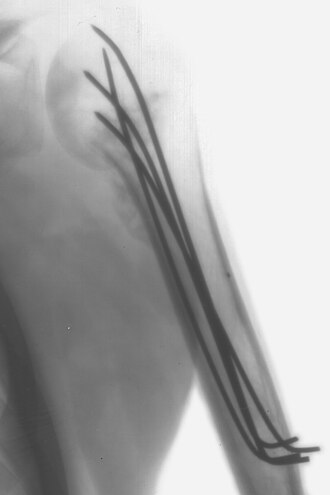

Intraoperativni RTG snimak nadlaktične kosti fiksirane Kirschnerovom žicom

Kirschnerova žica je sterilna, glatka, ne jednom kraju zašiljena, žica koja se koristi u ortopediji i raznim drugim oblicima kirurgije čovjeka i veterini. Žice nalazimo različitih debljina (1 do 2 mm) i koriste se kako bi držale zajedno pojedine dijelove kosti ili u skeletalnoj trakciji da omoguće hvatište na kosti. U upotrebu ju je uveo Martin Kirschner, 1909.g.